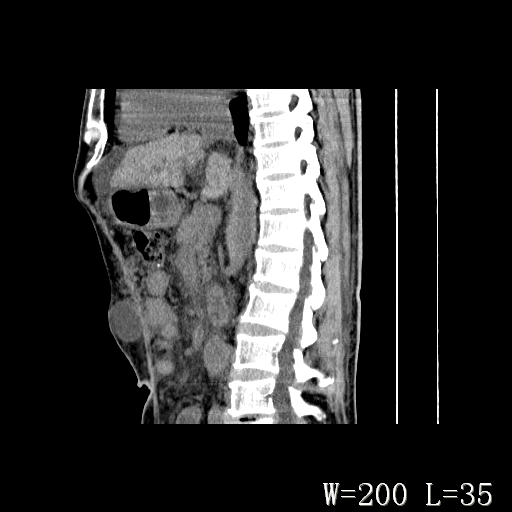

标题: CT27080:腹壁肿物?

男,52岁,门脉高压断流术后1年,发现腹部肿物2月。

1)前腹壁中线区(脐上方)囊性占位性病变,考虑淋巴囊肿。2)腹水。